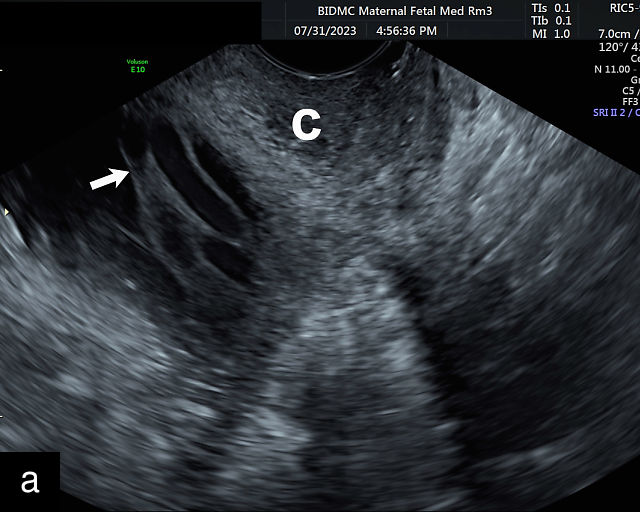

In the past, placenta previa was classified as complete, partial, marginal or low-lying.50,61 However, with advancements in ultrasound technology allowing precise assessment of the relationship between the placenta and the internal cervical os, the classification has been simplified.67 Placenta previa now refers to cases in which the placenta overlies the internal os to any degree, while low-lying placenta describes cases in which the lower placental edge lies within 2 cm of the internal os (Figure 5).51,66,67

5

Placenta previa and low-lying placenta. (a) Transabdominal grayscale ultrasound image suspicious for placenta previa. The placenta (PL) appears to overlie the internal cervical os (CX). Note the time stamp: 2:19:37. (b) Transvaginal ultrasound of the same patient taken approximately 50 minutes later. Note the time stamp: 3:10:25. The internal os and the lower placental edge are both clearly seen, and the placenta does not overlie the internal os. Because the lower placental edge is 1.93 cm from the internal os, it will likely resolve by the third trimester. (c) Transabdominal grayscale ultrasound of placenta previa. The placenta (p) covers the cervix, but the cervix, especially the internal os, cannot be visualized due to shadowing. (d) Transabdominal grayscale ultrasound of placenta previa. The placenta (p) covers the cervix (c) but shadowing obscures adequate visualization. The internal os is indicated by the arrow. (e) False-positive image of placenta previa on transabdominal grayscale ultrasound. The bladder (b) is full, pushing the anterior and posterior walls of the lower uterine segment (ls) together making it appear that the placenta (p) overlies the internal os of the cervix. In reality, the line depicted by the arrowheads is where the anterior and posterior walls of the lower segment are in proximity to each other. The cervix is much lower and is obscured by shadowing (c). (f) Transabdominal grayscale ultrasound image of placenta previa. The placenta (p) covers the cervix (c), but the cervix, especially the internal os, cannot be visualized due to shadowing. b, bladder. (g) Transvaginal grayscale ultrasound image of placenta previa. The placenta (p) completely covers the internal os (arrow) of the cervix (c). The internal os can be seen clearly. h, fetal head. (h) Transvaginal grayscale ultrasound image of posterior low-lying placenta (p). The lower placental edge is clearly seen and is 1.56 cm from the internal os (arrow) of the cervix (c). The placental edge and the internal os are clearly seen. h, fetal head. (i) Transvaginal grayscale ultrasound image of a posterior placenta previa (p). The internal cervical os is clearly seen (arrow). c, cervix. (j) Transvaginal grayscale ultrasound image of an anterior placenta previa (p). The internal cervical os is clearly seen (arrow). c, cervix; h, fetal head. (k) Transvaginal grayscale ultrasound image of a posterior placenta that was thought to be low-lying on transabdominal sonography but could not be adequately assessed. This examination clearly shows the lower edge of the placenta (p) to be 2.18 cm from the internal os (arrow) of the cervix, firmly establishing that the placenta is not low-lying and allowing the patient to undergo labor safely and deliver vaginally. c, cervix. (l) Transvaginal grayscale ultrasound image of placenta previa. The placenta (p) completely covers the internal os (arrow) of the cervix (c). The internal os can be seen clearly.

This distinction is critical in determining the mode of delivery.49,51 All patients with placenta previa persisting into late pregnancy require cesarean delivery to avoid complications such as severe bleeding.50,60,61 Studies suggest that patients with a lower placental edge located more than 1 cm from the internal os may safely attempt a vaginal delivery without a significant increase in bleeding risk.68,69,70,71

Most cases of placenta previa will be suspected prenatally by transabdominal ultrasound.49 However, this approach has several limitations and may be inaccurate.72,73,74 because the relationship between the placenta and the internal cervical os may be difficult to assess by transabdominal ultrasound.72,73,74 The bladder may be full, pushing the anterior and posterior walls of the lower uterine segment together, falsely creating the impression of a placenta previa (Figure 5e).61 There may be considerable shadowing, including by the fetal presenting part, which may limit the accuracy of transabdominal ultrasound (Figure 5d,f).75 Posterior placentas may be more difficult to assess.

Transvaginal ultrasound overcomes these limitations (Figure 5g–l).72,73,74,76 The probe is inserted into the vagina and therefore is closer to the region of interest.51,61 In addition, transvaginal transducers have higher frequencies and superior resolution compared to transabdominal transducers. Transvaginal ultrasound is safe and is not associated with increased bleeding.72,73,74,75,76 As such, transvaginal ultrasound should be the imaging modality of choice whenever there is suspicion of placenta previa.49,67,77